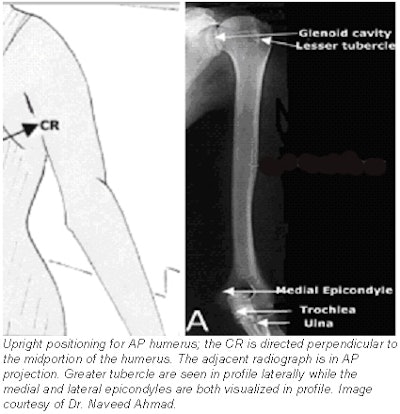

- Central ray (CR): perpendicular to the midportion of the humerus and the center of the cassette.

Evaluation criteria for AP projection of humerus

- AP projection of the entire humerus, including the shoulder and elbow joints.

- Long axis of the humerus should be aligned to the long axis of the IR.

- A true AP projection is evidenced at the proximal humerus by the following:

- The greater tubercle is seen in profile laterally.

- The humeral head is partially seen in profile medially, with minimal superimposition of the glenoid cavity.

- The distal humerus should show both lateral and medial epicondyles visualized in profile.

- CR and center of the collimation field should be to the approximate midpoint of the humerus.

- Optimal density and contrast with no motion and sharp cortical margins. Bony trabecular markings should be demonstrated at both the proximal and the distal portions of the humerus.